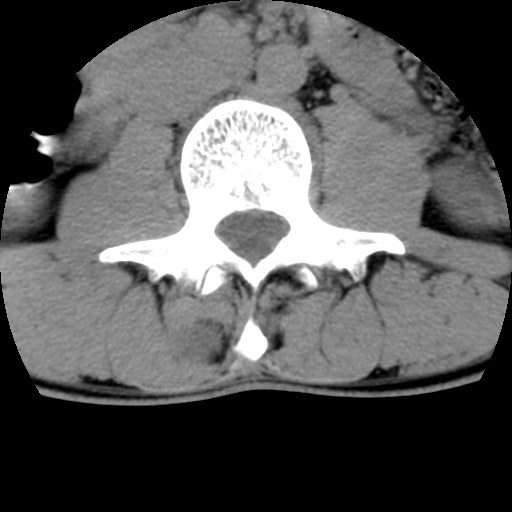

标题: CT16890:男,腰背痛.

男,腰背痛

本人诊断1tb2包虫,请会诊

1)右侧竖脊肌稍低密度肿块伴钙化(性质待定),不排除肿瘤可能;建议行进一步检查。2)腰椎间盘突出。

1.右侧竖脊肌软组织肿块伴团块状钙化,首先考虑血管瘤可能性大;建议行进一步检查;2。腰椎间盘突出。